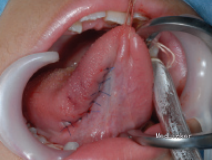

患者八岁,发现舌部有一逐渐生长的肿物一个月,没有其他不适。患者患有共济失调 - 毛细血管扩张症。

检查发现舌下有一隆起,约1.2*1cm大小,未影响舌功能和运动,唾液分泌正常,周围淋巴结无肿大。 影像检查显示右舌有一不规则圆形肿物,边界不清。

初步诊断为涎腺肿瘤,如多形性腺瘤。然而,由于患者被诊断为共济失调 - 毛细血管扩张症,考虑恶性淋巴瘤的可能性较大。全麻下手术切除,术后配合化疗。病理结果显示为弥漫性大B细胞淋巴瘤。